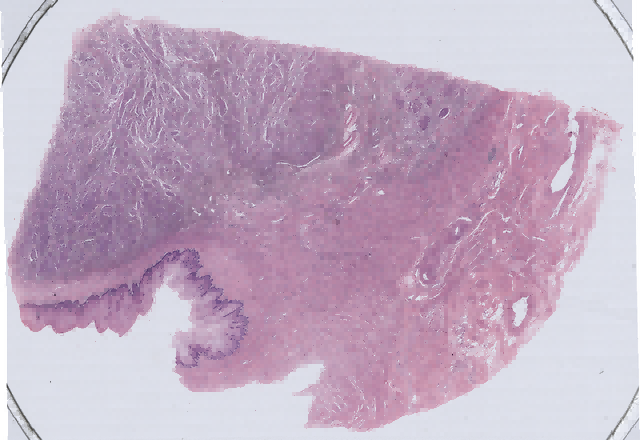

子宫颈瘤数字切片